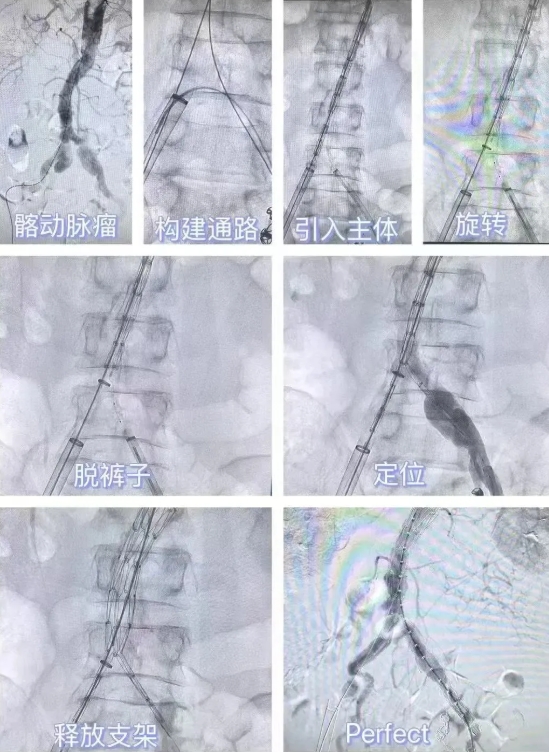

术中,面对高龄、多病共存、血管条件差的挑战,介入团队制定了精细方案:

1. 保住功能:髂动脉负责盆腔脏器及下肢供血,传统手术常需牺牲分支血管;

2. 精准“排雷”:通过血管造影锁定腹主动脉瘤(伴血栓)、双侧髂动脉瘤位置;

3. 微创“拆弹”:植入覆膜支架隔绝瘤腔,栓塞左侧髂内动脉防返流;

4. 疏通“生命线”:球囊扩张成形术改善下肢血流。